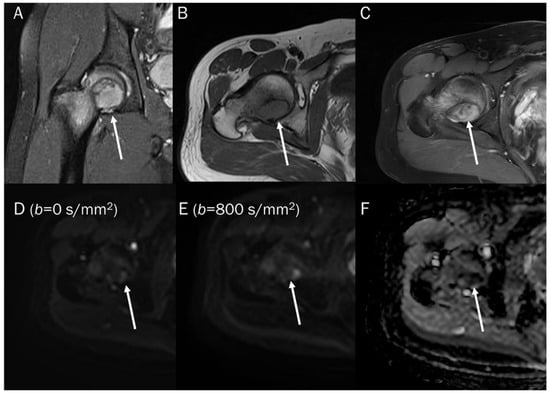

7.1. Cyst

| Benign cyst | T2 shine-through | Free water |